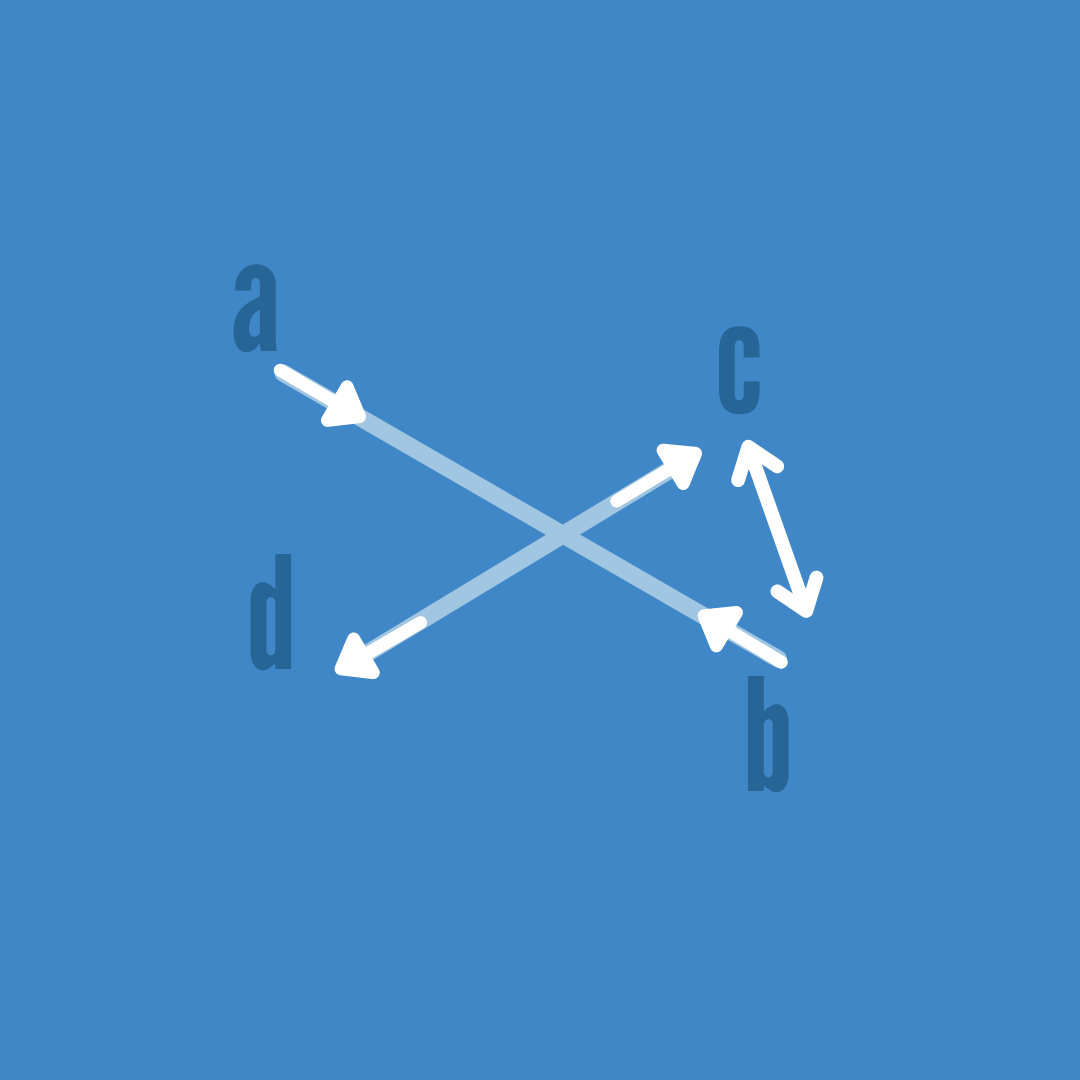

Esta asimetría se representa con líneas abdominales que van desde la última costilla anterior, hasta la cresta ilíaca contraria.

El músculo oblícuo externo derecho (a) y el oblícuo interno izquierdo (b) se hallan sobreelongados. Y los contrapuestos (c) y (d) se hallan en acortamiento.